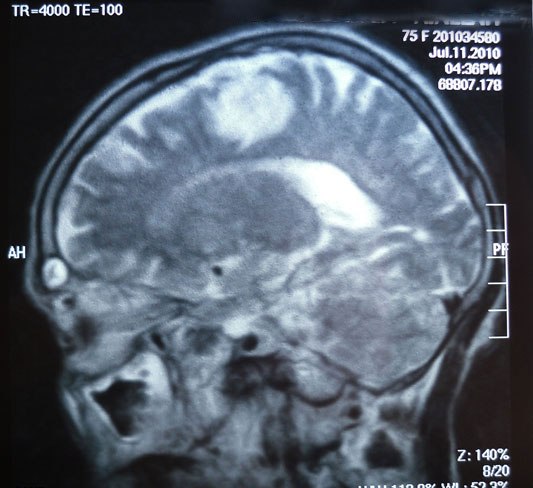

A 74 year-old female, diabetic, complained of

unilateral right upper limb fits that became generalized.

CT And MRI brain ordered with the above photos results.

Left high parietal subcortical lesion with mass effect manifested as

effacement of the adjacent sulci, mostly neoplastic mass lesion for

better assessment by enhanced MRI study.